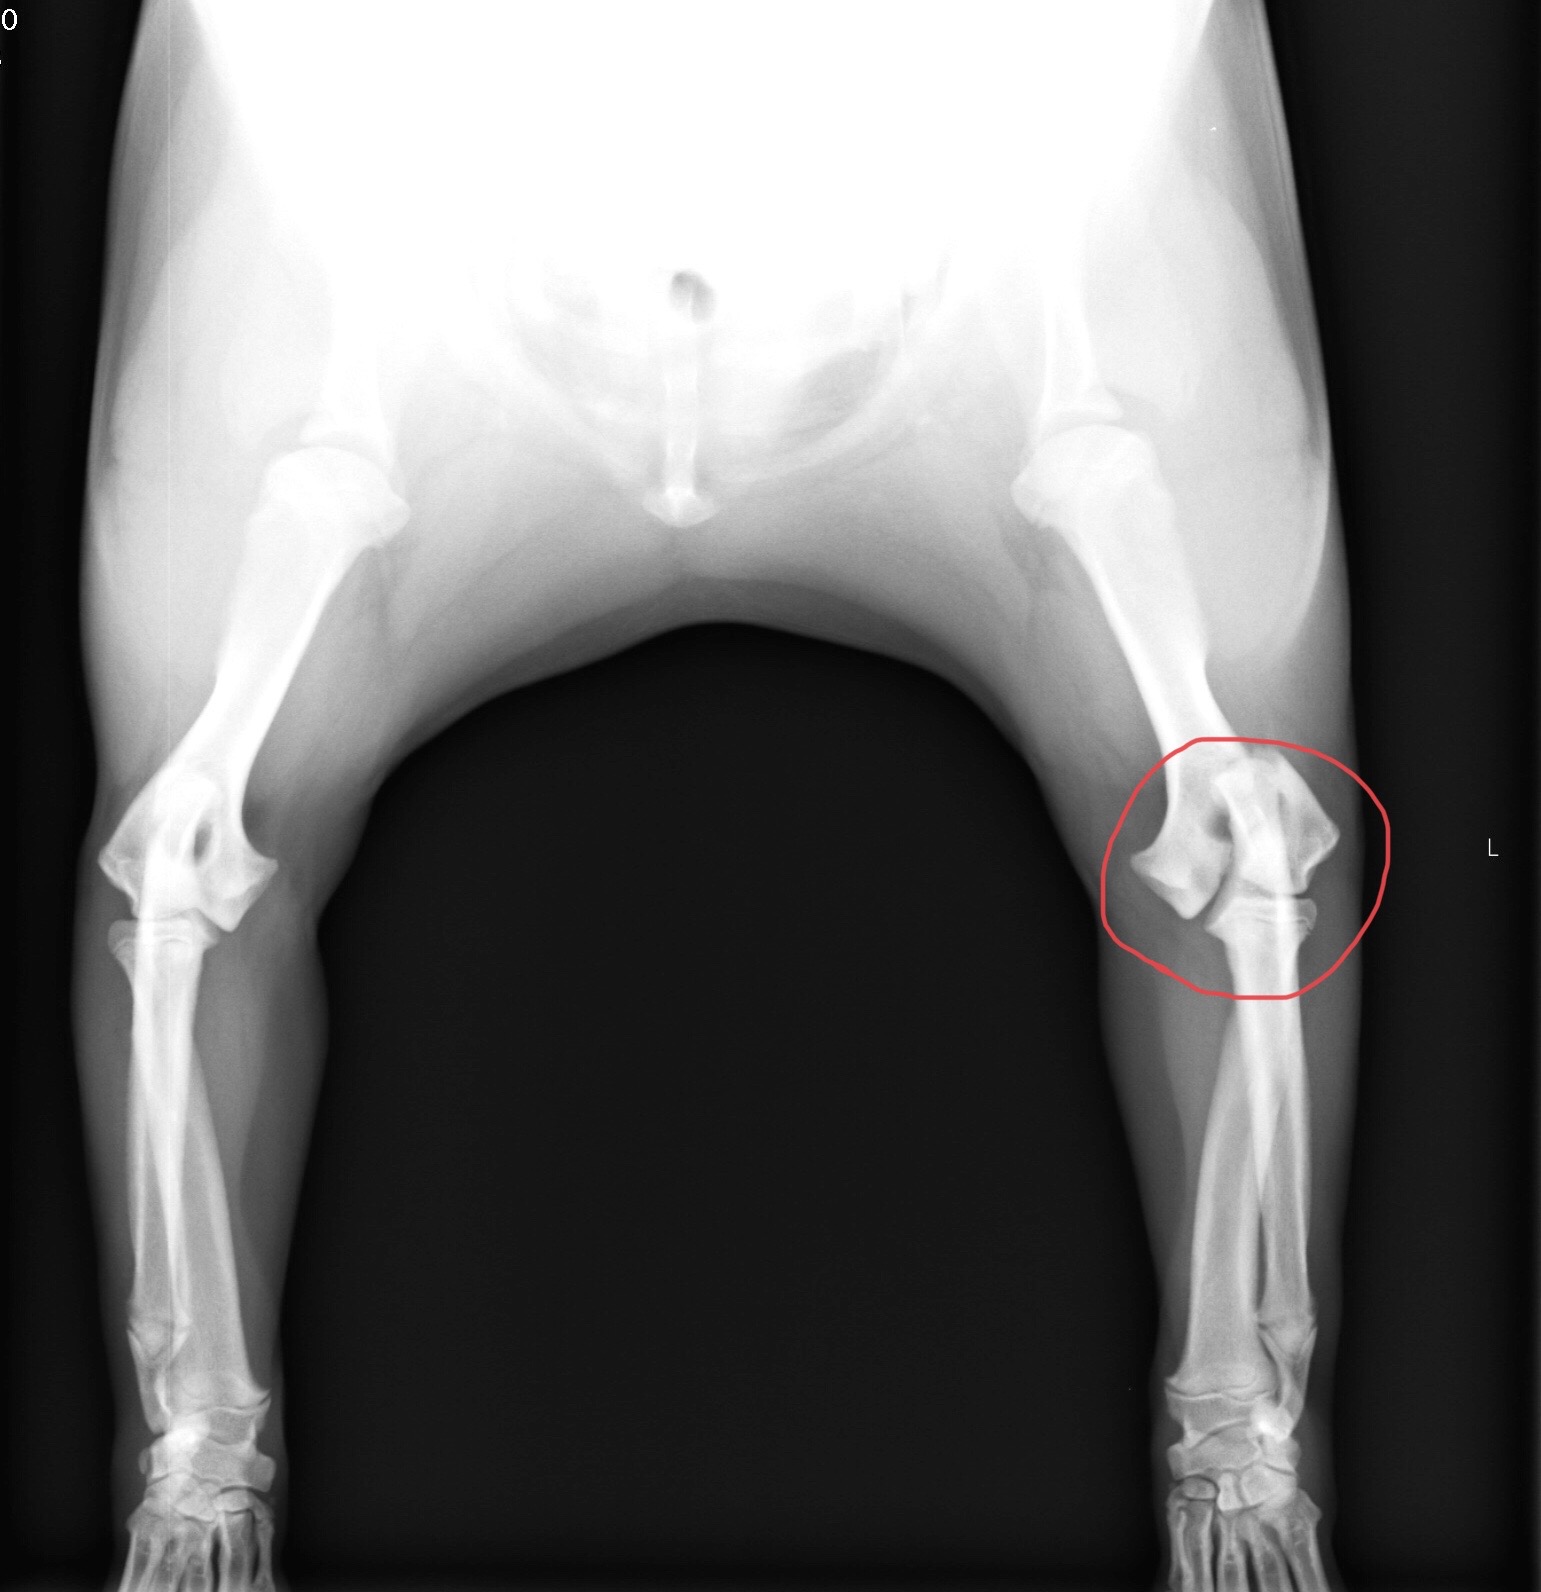

犬の上腕骨外顆の成長板骨折の一例

抱っこしていた犬が飛び降りて着地を失敗。そのまま足の骨を折ってしまった…。 そんな話を聞いたことがある方もいらっしゃるのではないでしょうか。 犬は比較的骨折をしてしまうと言われていますが、特に若齢の犬は骨が成長途中のため折れやすくなっています。 本症例は10歳避妊雌のフレンチブルドッグです。 オーナー様が抱っこしている最中に、腕から飛び降りて肘を強打。その後、左前肢を挙上しているとの主訴で来院されました。 来院時も左前肢を挙上した状態で、左の肘あたりを触ると軽度の骨の動揺が認められました。 肘部のX線検査にて左上腕骨外顆の成長版骨折が認められました。